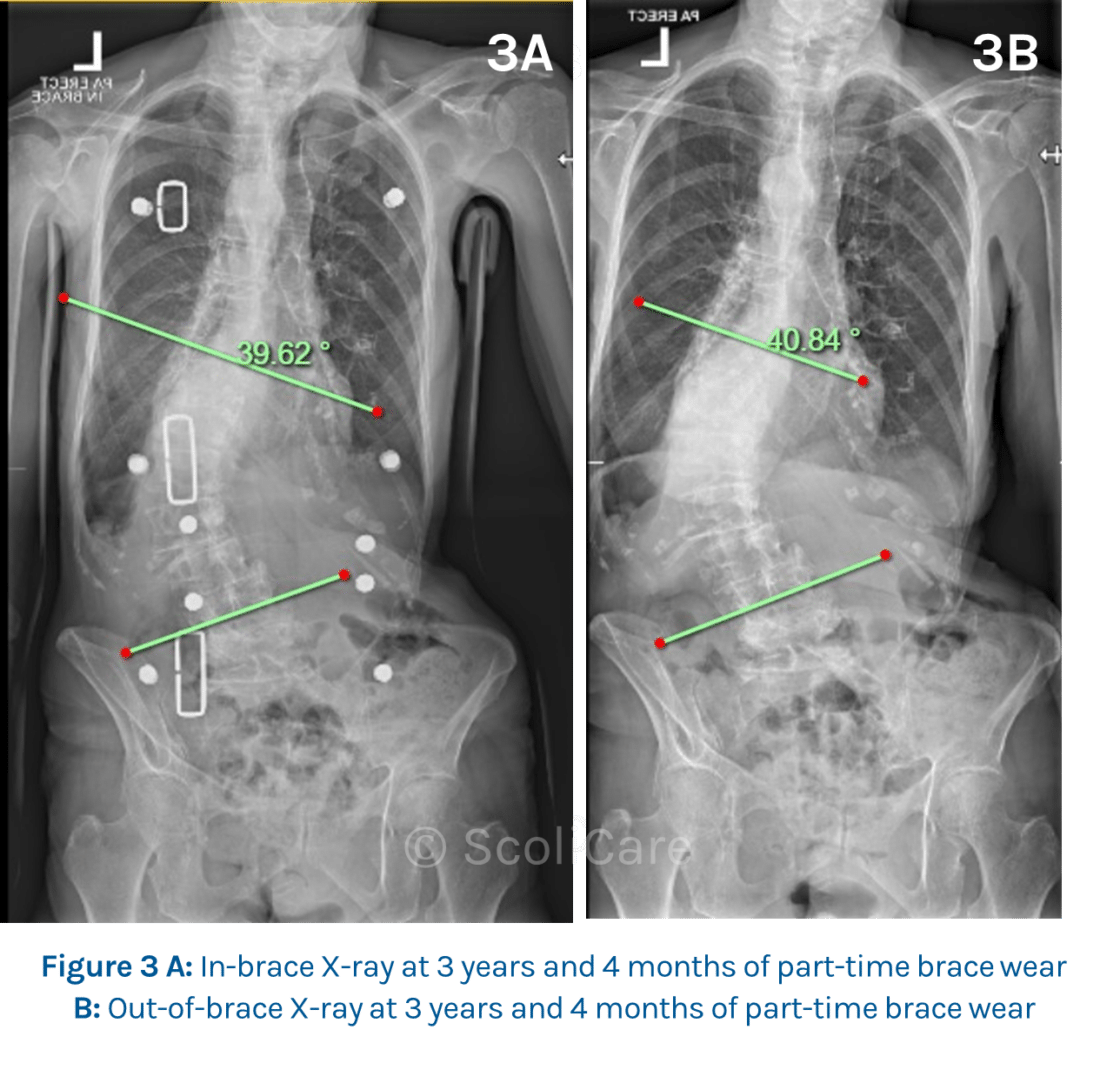

The patient’s spine responded favourably to the treatment with the curve stabilized at 40° in-brace and 41° out of brace after 3 years and 4 months of part-time brace-wear (Figure 3A and 3B).